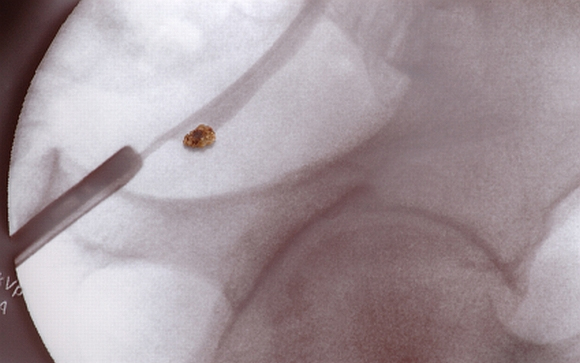

A vesekő tünetei és kezelése

Gyakori betegség, minden tizedik embert érint valamikor élete során a vesekő. A legmagasabb az arány az Egyesült Államokban, ahol az elmúlt két-három évtizedben folyamatosan emelkedett az érintettek száma. Mik a tünetei és hogyan kezelhető? Kiderül cikkünkből.

A vesekövek ásványi sóból képződött kicsi és kemény lerakódások a vese belsejében. Amikor a vizelet túl koncentrált, az már egy jele lehet a későbbi vesekőképződésnek. Először kristályok képződnek, amelyek idővel nagyobb kővé érnek össze.

A vesekő kialakulásának pontos oka nem ismert. Különböző típusú vesekövek léteznek, amelyek utalhatnak az eredetre. Leggyakoribb formája a kálcium-kő, amelyet a kalcium-oxalát okoz. Az oxalát az élelmiszerekben természetes módon előforduló vegyület, ezért bármi amiben sok található belőle, növeli a vesekő kialakulásának kockázatát.

Elegendő folyadék fogyasztásával azonban sokat lehet tenni a megelőzésért. Eltávolításának módja a kő méretétől függ. Ha kisebb, akkor jó eséllyel spontán módon eltávolodik. Sok víz fogyasztása és fájdalomcsillapító szerek szedése segíthet ebben. Nagyobb kövek esetén azonban invazív beavatkozásokra lehet szükség. A műtét során a húgycsövön keresztül vezetnek fel egy csövet, amely szétzúzza a nagyobb köveket kisebb darabokra, amelyek könnyebben eltávolodnak a szervezetből.